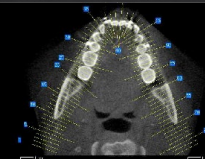

segmenting the CBCT imaging

3d modeling of bone used for planning

pathology preventing tooth eruption